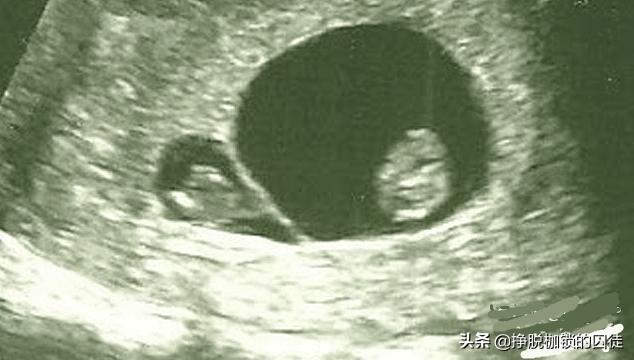

我们知道,在孕早期,妊娠6~7周超声检查就可以观察到胎囊的存在,7~8周可以看到胎心搏动,超声检查正是通过观察胎囊和胎心来确定妊娠是单胎还是多胎。

如上所述,在孕早期,妊娠6~7周超声检查可以观察到胎囊的存在,7~8周可以看到胎心搏动,超声检查正是通过观察胎囊和胎心来确定妊娠是单胎还是多胎。

如果在之后的超声检查中,观察到原本存在的胚胎或胎儿数量减少,就可以诊断为胞胎消没综合征。

有一些“压扁胎”可以通过超声检查观察到。